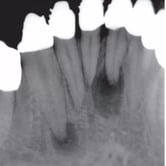

Lesión Endo-Perio Combinada

Una lesión endo-perio combinada es una condición en la que hay tanto una infección de la pulpa como una enfermedad periodontal.

Los pacientes pueden experimentar dolor, hinchazón y movilidad dental.

El tratamiento incluye tanto el tratamiento de conducto como el tratamiento periodontal para abordar ambas infecciones. La coordinación entre el endodoncista y el periodoncista es esencial.